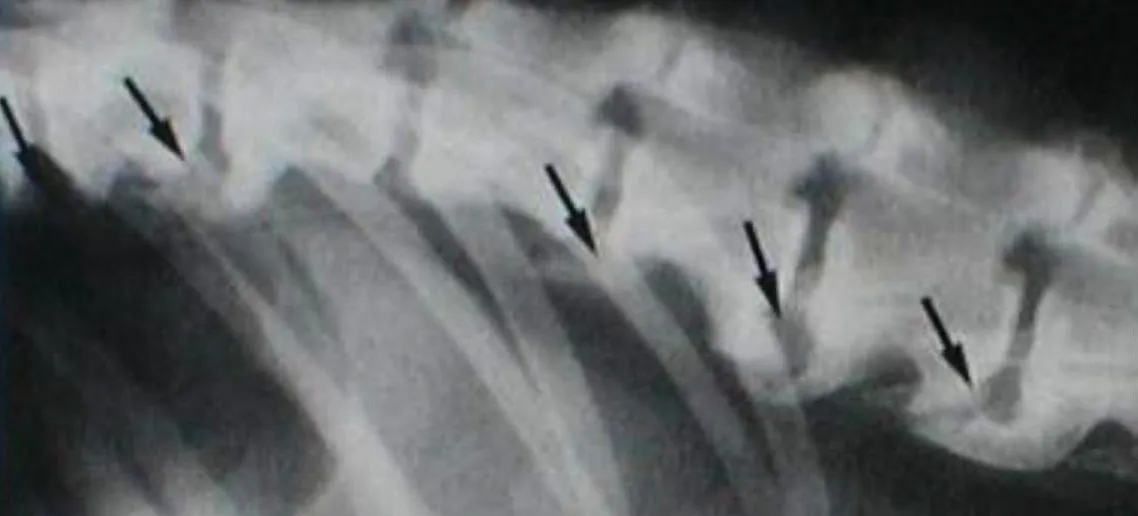

Da es sich um eine Erkrankung der Knochen handelt, sind die Veränderungen durch Röntgen sichtbar zu machen:

Auf dem Bild kann man erkennen, dass bereits richtige "Nasen" (schwarze Pfeile) an den der Wirbel entstanden sind und diese sich miteinander verbunden haben. Die Verknöcherungen treten bei Spondylose an der Unterseite der Wirbel auf, wie auf dem Bild zu Sehen. Es verknöchern NICHT die oberen Enden der Wirbel miteinander (wie bei der Pferdeerkrankung „kissing spines“ ).